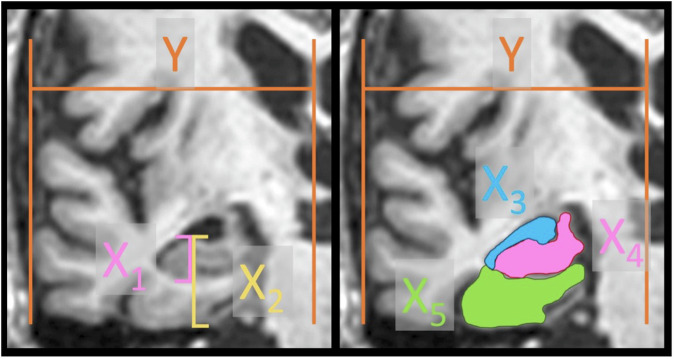

The medial temporal lobe atrophy (MTA) score is used for visual assessment of MTA on radiological images in suspected neurodegenerative dementia. Although volumetric tools are available, many radiologists still use visual scoring and compare to reference images. Numerous such example images are found online on educational websites and in scientific articles. The aim of this study was to compare congruencies between MTA scores of publicly available sample images with normalized heights and areas of relevant brain structures, measured in the same images.

Method: Systematic online searches yielded 148 individual sample images. The height and area of relevant brain structures were manually delineated, normalized, and compared with regard to the displayed MTA score.

Results: The normalized heights and areas showed correlation with MTA but with considerable overlap between adjacent scores, especially when comparing heights. Also, displays of the MTA score were more consistent with the area of the temporal horn than with the hippocampal area.

Conclusion: There is considerable overlap between adjacent scores in publicly available pictorial displays of the MTA grading system. Insufficient congruency leads to confusion and reduces inter-rater reliability. We also found that publicly available images are more consistent with temporal horn area than the hippocampus, which means that ventricular size may bias the grading. This can impede relevant differential diagnostics, especially regarding normal pressure hydrocephalus. Here, we present lectotype images selected specifically with regard to the hippocampal area.